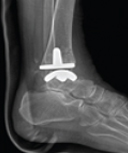

발목관절 전치환술

골관절염, 외상으로 인한 관절염 류마티스성 관절염 발생시 관절의 손상된 부분을 인체공학적으로 고안된 인공관절로 대체하여 원래의 신체구조를 복원시키고 통증을 완화해주는 수술입니다.

- 수술후